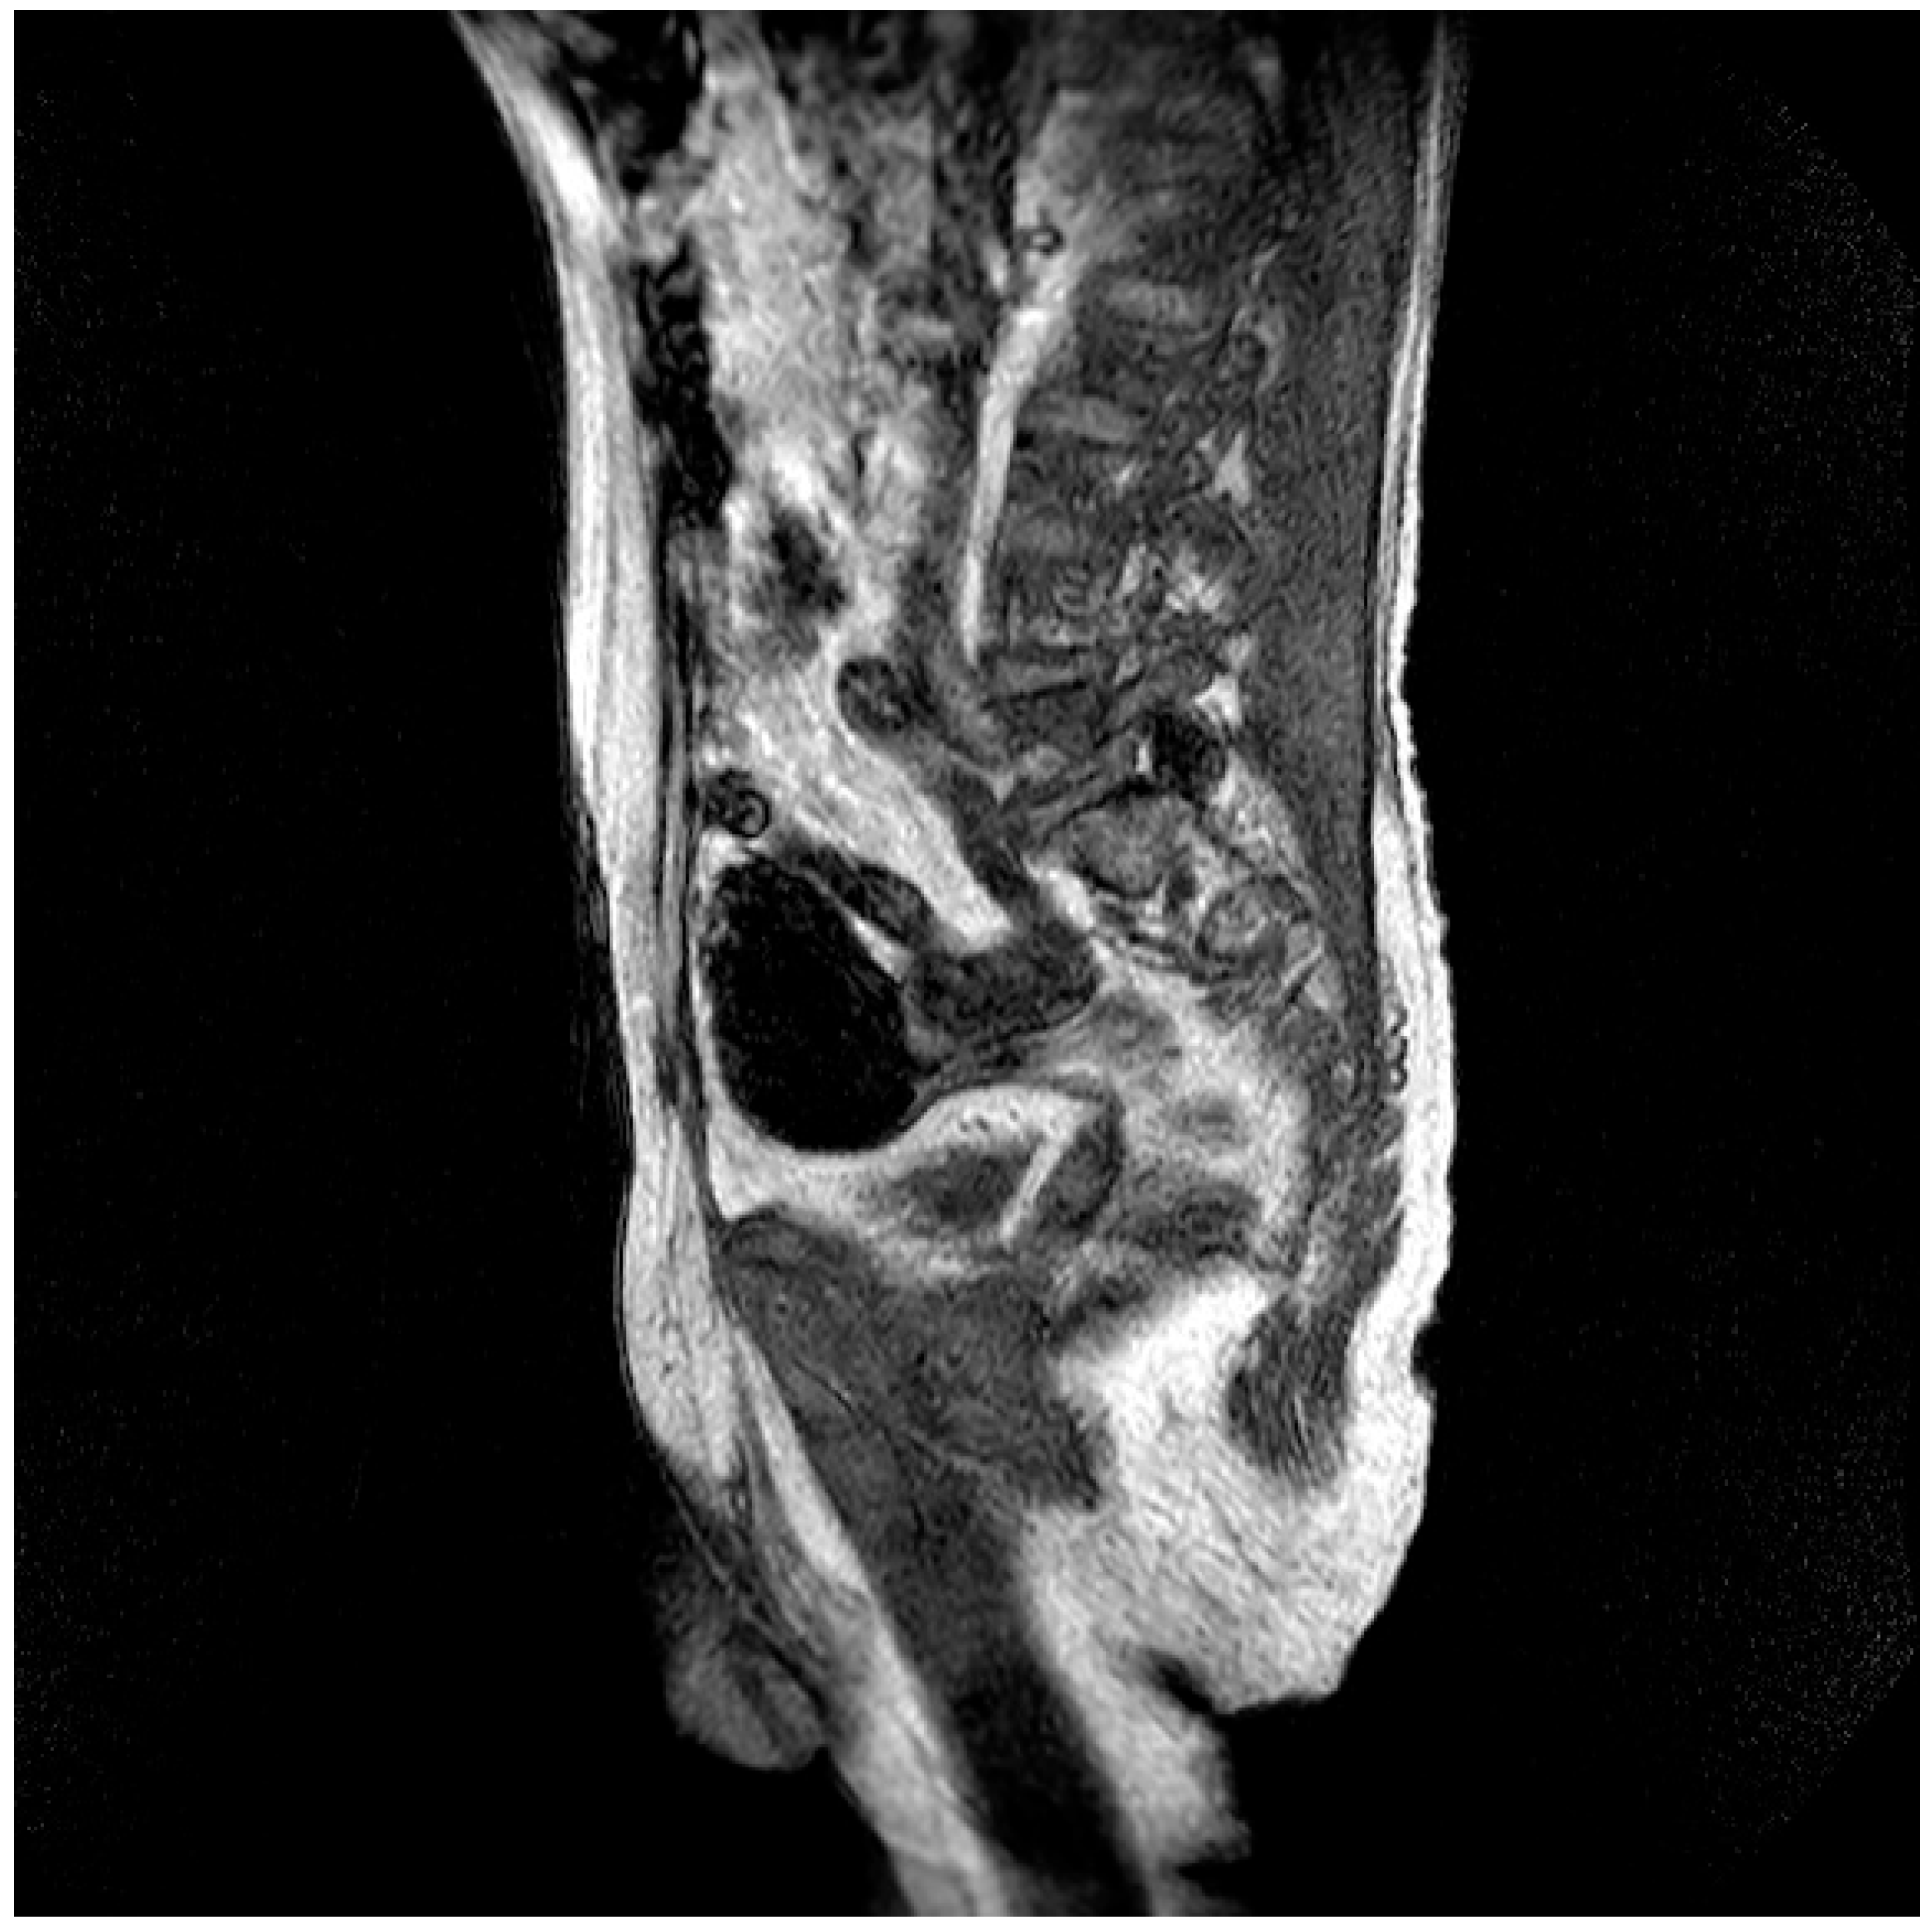

| Pt 7, M, 71, 2025 | HHD, cognitive involutional syndrome | High fever, headache, confusion, worsening motor difficulty with lower limb weakness | +/+ | Neg | Neg | Neg | ICH of the occipital horns of the lateral ventricles (Figure 2) | Diffuse meningoencephalitis, with involvement of the cauda extremity roots. ICH of the occipitopolar and bihemispheric mid-posterior cingulate sulci, the left temporoparietal carrefour, and the fourth ventricle, occipital horns, and pericerebellar cistern. Posterior dorso-lumbo-sacral, anterior dorso-lumbar (up to L1), and sacral epidural hematoma (Figure 3 and Figure 4) | DEX, Igs | Gradual clinical improvement, however lower limb weakness persisted | Transferred to a rehabilitation facility 34 days after hospital admission. | |

Figure 2.

Evidence of an extensive epidural spinal cord hematoma on spinal MRI (Table 1, patient 7).

Three male patients with a median age of 71 years (range 68–74), presented ICH associated with WNE (Table 1, patient 2, 7, 9). Two male patients, the first 74-year-old (Table 1, patient 2) suffering from arterial hypertension and the second 68-year-old (Table 1, patient 9) suffering from diabetes mellitus and post-ischemic dilated heart disease, died after 13 and 21 days, while the third patient (Table 1, patient 7) was transferred to a neuromotor rehabilitation facility after 34 days of hospitalization. This patient, before admission to the hospital, presented age-related brain involution symptoms and suffered from chronic hypertensive heart disease. The reasons for admission to the emergency room were worsening motor difficulties with weakness in the lower limbs, a rapidly worsening state of confusion, high fever, and an episode of hypertensive peak. Repeated studies of the brain and spinal cord, using computed tomography (CT) scans and magnetic resonance imaging (MRI), have documented a very complex picture, characterized by diffuse meningoencephalitis, with a diffuse flogistic involvement of the pachy-leptomeninges and the equine cauda roots, blood deposits in the occipitopolar and bihemispheric mid-posterior cingulate sulci, the left temporoparietal carrefour, the fourth ventricle and occipital horns and the pericerebellar cistern. There was also evidence of a diffuse posterior dorso-lumbo-sacral, anterior dorso-lumbar (up to L1) and sacral spinal cord epidural hematoma. Diffuse hemosiderin coating was present on the dural surface in the dorso-distal posterior lumbo-sacral and anterior lumbo-sacral regions, as well as at the anterior 8th-10th level. Serology for WNV was positive, while WNV RNA testing in CSF, blood, and urine was negative. Treatment included two 5-day cycles of high-dose immunoglobulins and the use of dexamethasone (Table 1, patient 7).